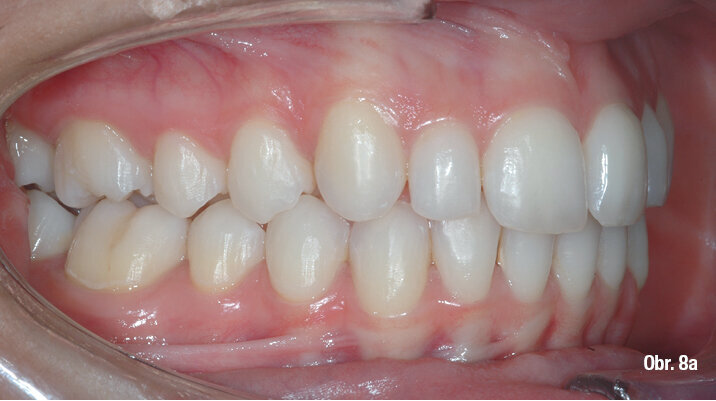

Klinický výsledek byl vynikající, postavení molárů i špičáků v I. třídě, vyhovující překus a předkus. I profil dolní třetiny obličeje byl výrazně lepší.

Na překrytí kefalometrických snímků je zřejmá distalizace molárů o 6 mm bez výraznějšího sklonu a s ideálním bukolingválním sklonem řezáků. Tahy druhé třídy umožnily protrakci mandibuly o 1,5 mm. Jako retenční aparáty jsme zvolili Vivera retainery (Align Technology) (obr. 6, 7a–c, 8a–c).